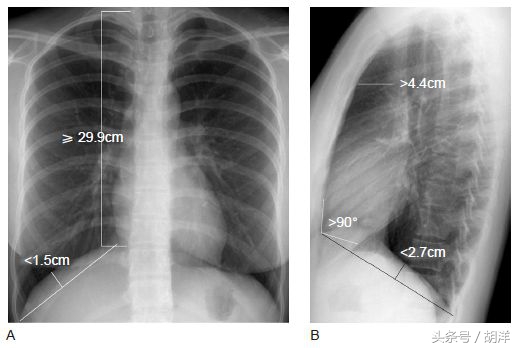

肺气肿患者的胸廓各个指标超过标准值